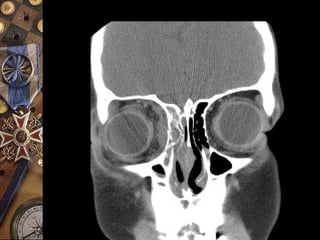

SINUSITIS DIAGNOSTICO

 TRANSILUMINACION DE SENOS

 RAYOS X

SINUSITIS COMPLICACIONES

EXTRACRANEALES:

 CELULITIS ORBITARIA

 SIND. DE FISURA

ORBITARIA SUPERIOR

 OSTEOMIELITIS

INTRACRANEALES:

 MENINGITIS

 ABSCESOS:

EPIDURALES

SUBDURALES

CEREBRALES

 TROMBOSIS DEL

SENO CAVERNOSO

CELULITIS ORBITARIA